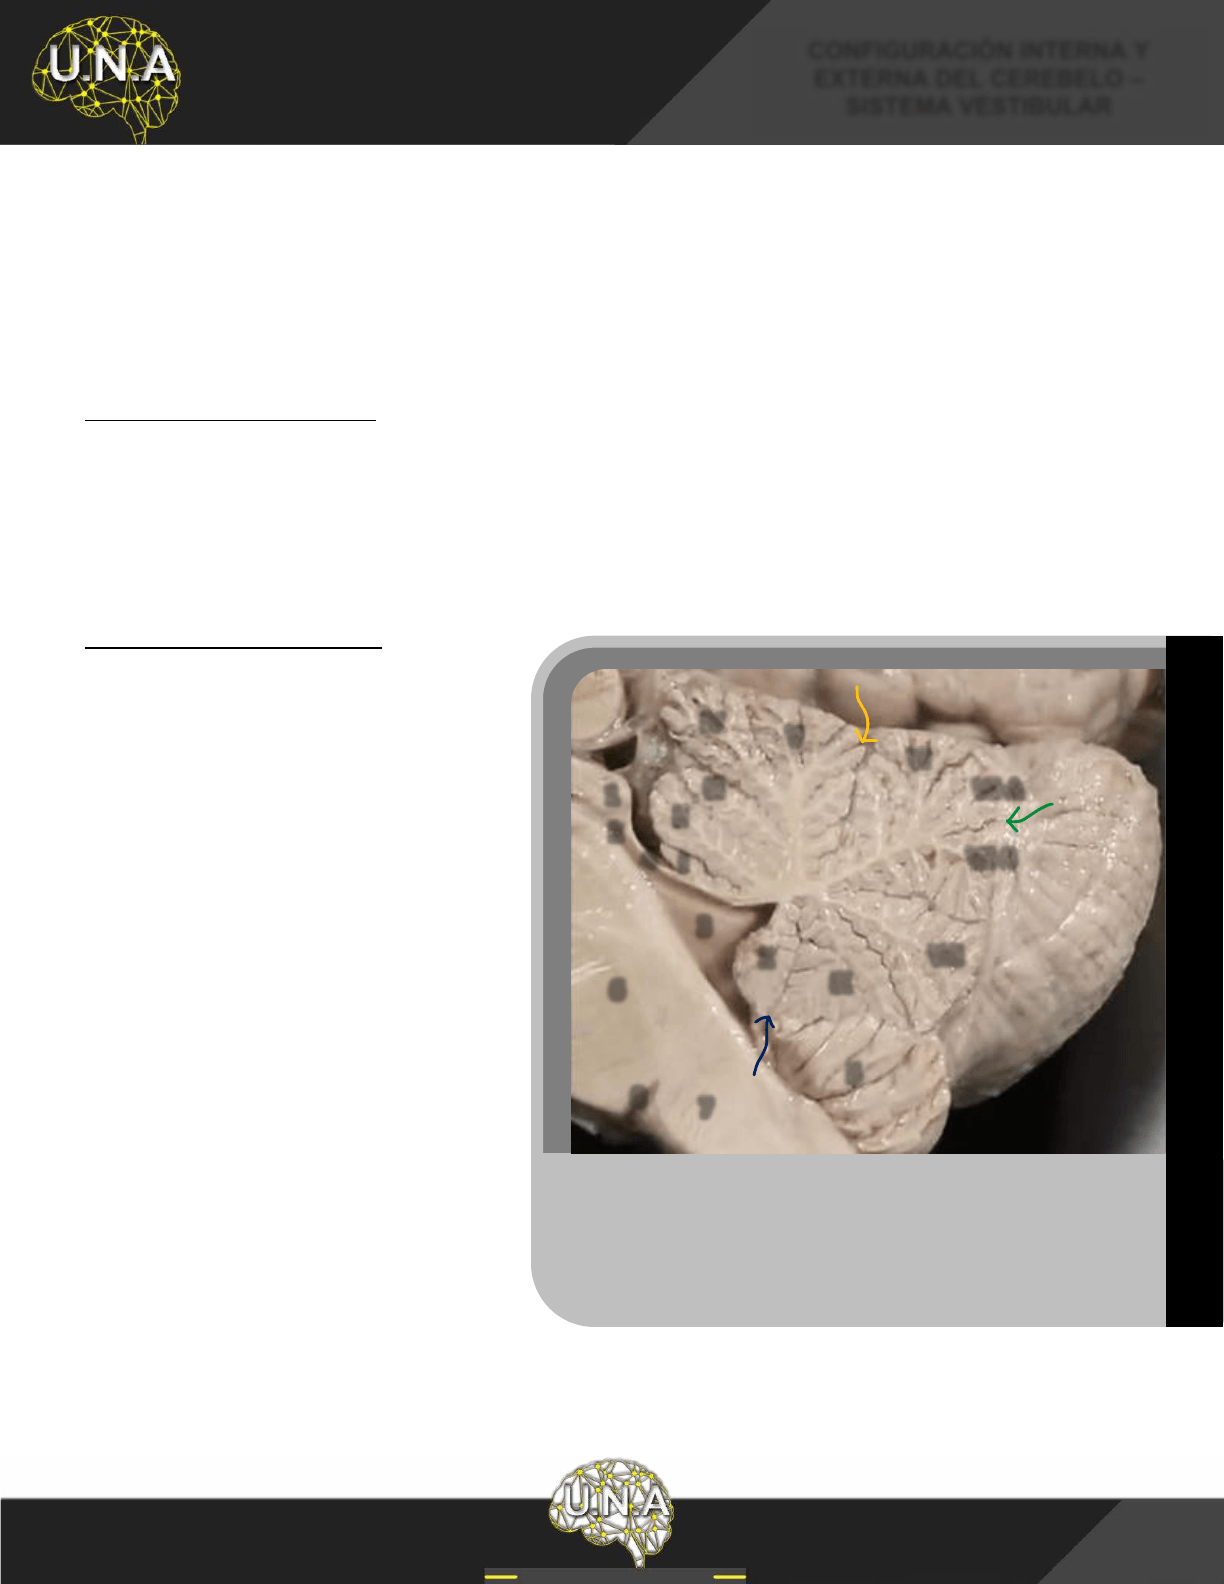

PISO DEL CUARTO VENTRÍCULO

El piso del cuarto ventrículo, también llamado fosa romboidea, corresponde a la cara dorsal del puente y la

médula oblongada, para describirlo se lo divide en dos triángulos uno superior y otro inferior, opuestos por

sus bases, separados por las estrías medulares (fibras blancas que emergen de la línea media y se dirigen

hacia los tubérculos acústicos).

Vista dorsal del cerebelo y tronco del encéfalo. 1) Colículo inferior; 2) Pedúnculo

cerebeloso superior;

3) Lobulillo cuadrangular (segmento anterior); 4) Lobulillo

cuadrangular (segmento posterior);

5) Lobulillo semilunar superior; 6) Lobulillo

7) Núcleo dentado; 8) Vallécula; IV-V) Culmen; VI) Declive;

Folia; VII-B) Tuber; Línea de puntos superior: Surco primario; Línea de

: Surco horizontal.